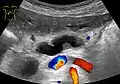

Compression, obstruction or inflammation of the pancreatic duct may lead to acute pancreatitis. The most common cause for obstruction is the presence of gallstones in the common bile duct, a condition called choledocholithiasis. Obstruction can also be due to duodenal inflammation in Crohn's disease.[7] A gallstone may get lodged in the constricted distal end of the ampulla of Vater, where it blocks the flow of both bile and pancreatic juice into the duodenum. Bile backing up into the pancreatic duct may initiate pancreatitis.[8] The pancreatic duct is generally regarded as abnormally enlarged if being over 3 mm in the head and 2 mm in the body or tail on CT scan.[9] Pancreatic duct or parts of pancreatic duct can be demonstrated on ultrasound in 75 to 85% of people.[10]